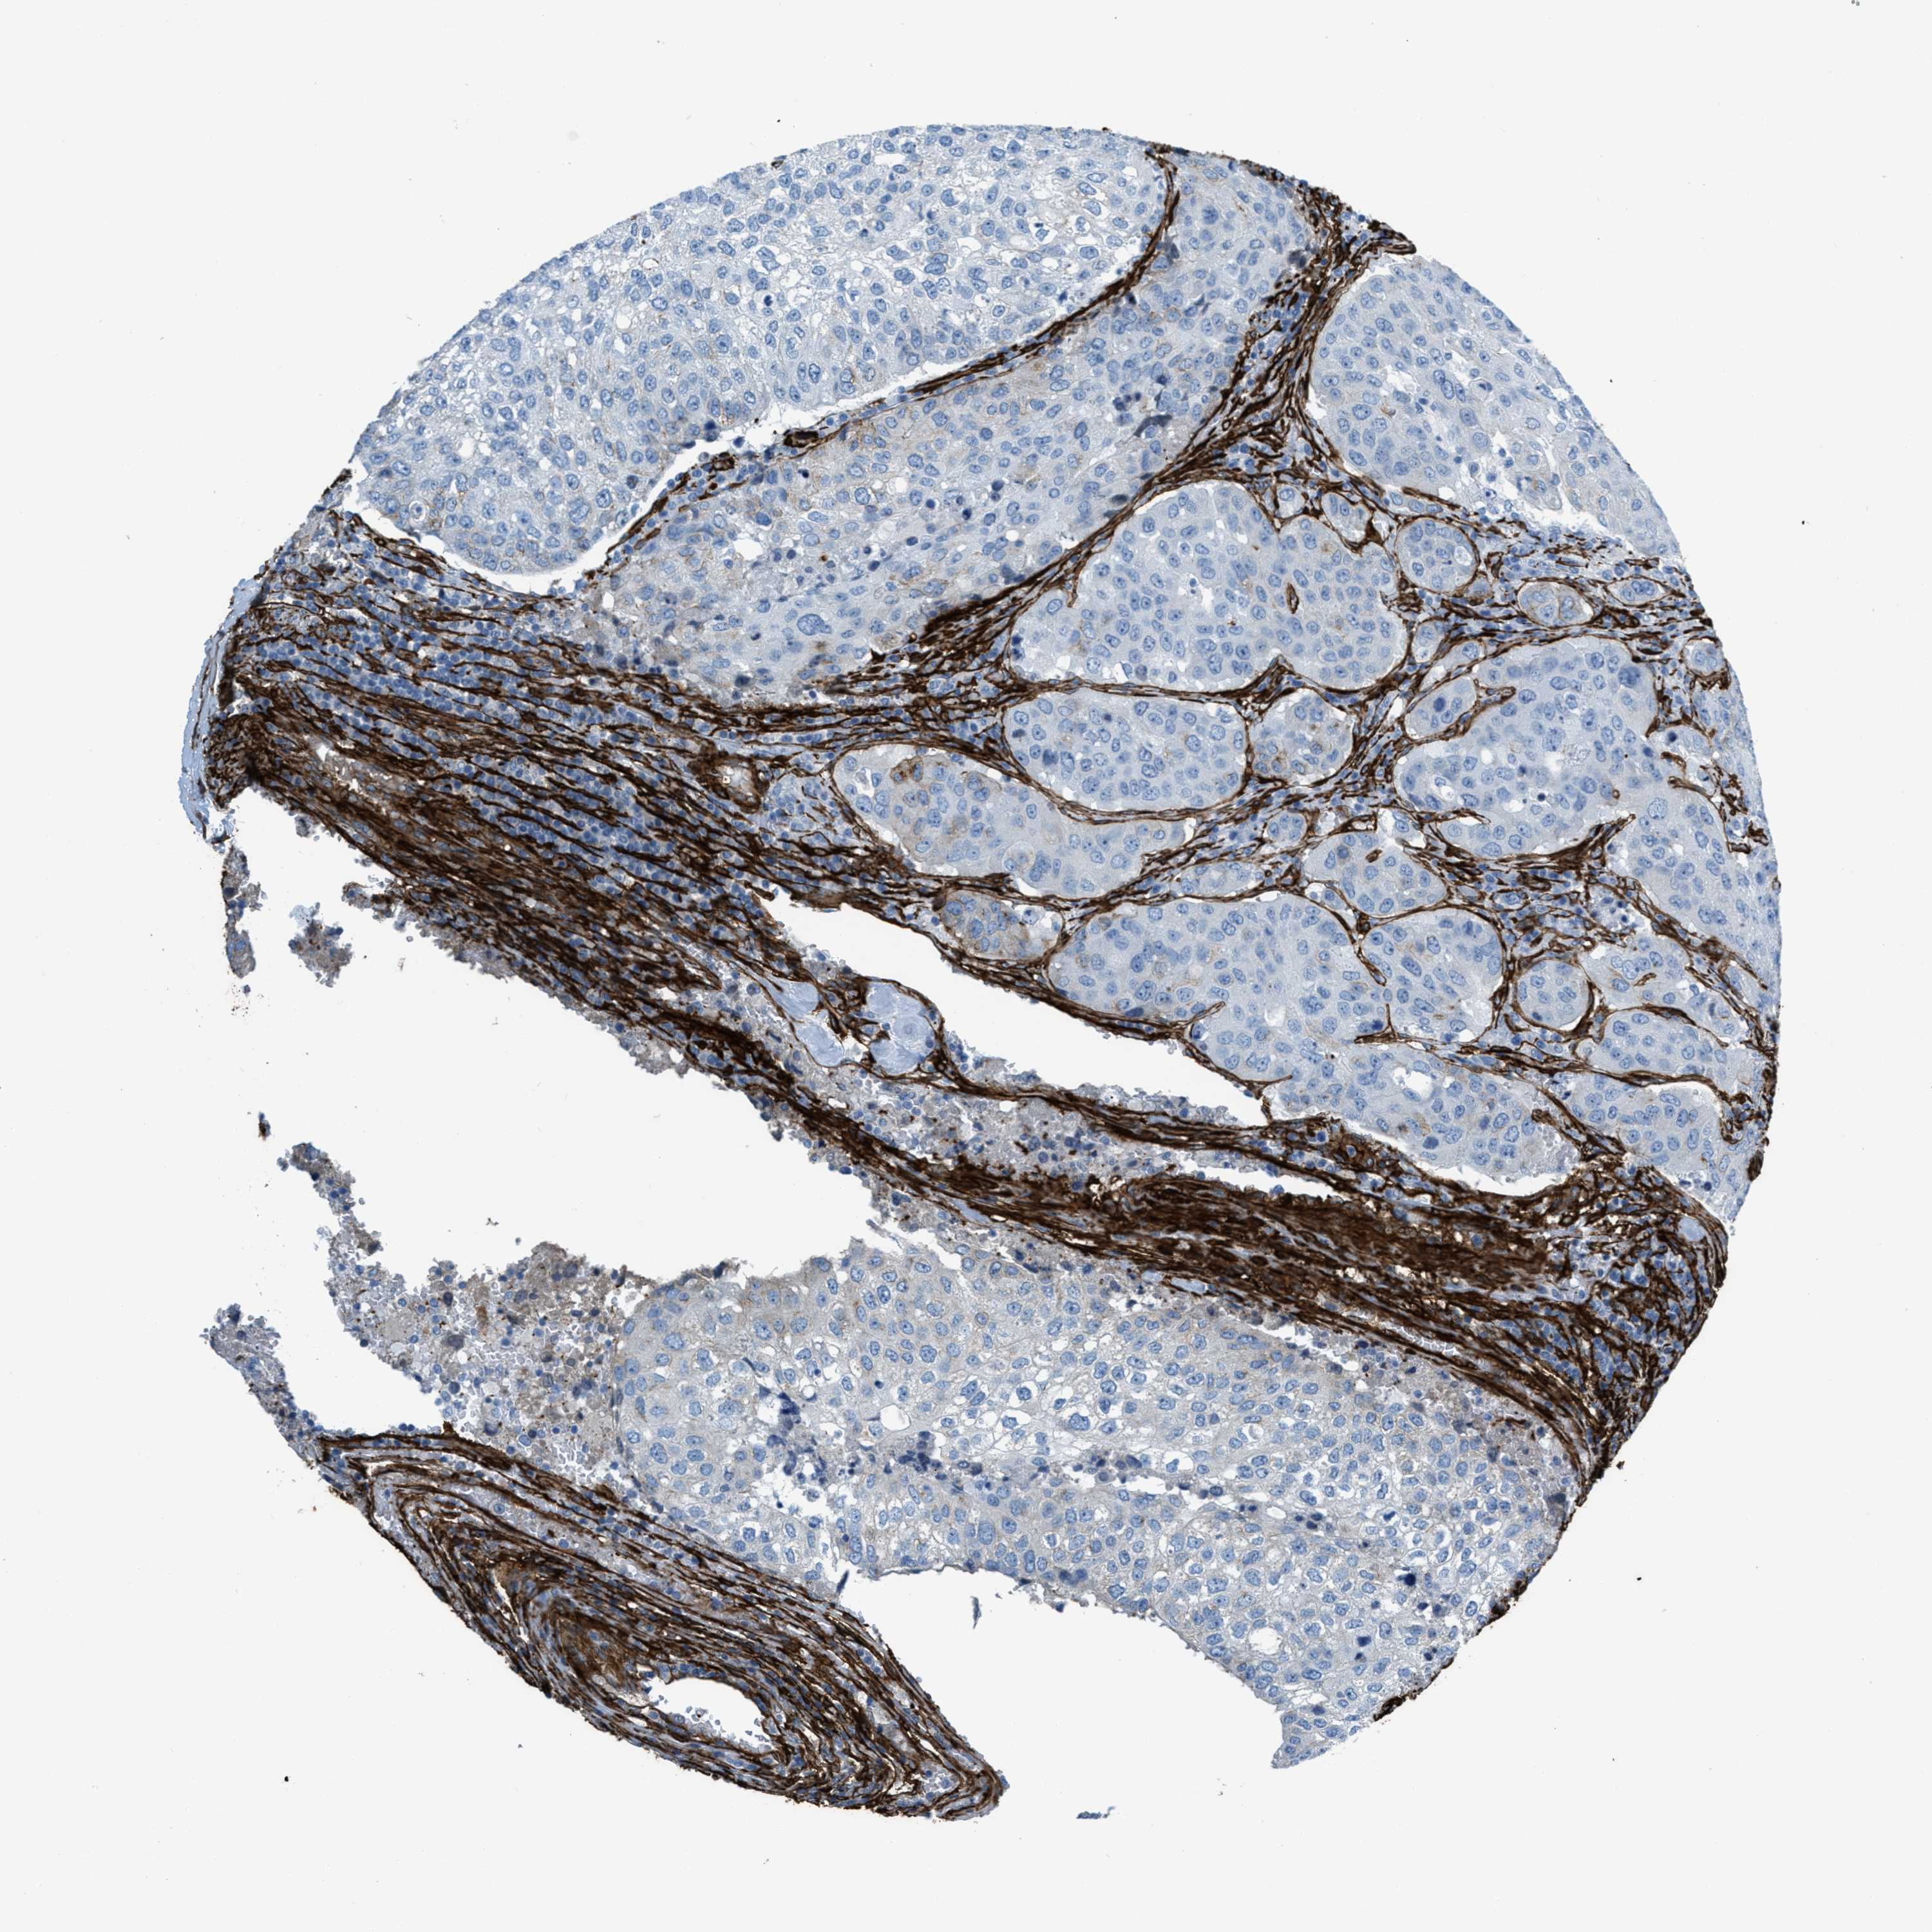

UROTHELIAL CANCER - Protein expressioni

A mouse-over function shows sample information and annotation data. Click on an image to view it in a full screen mode. Samples can be filtered based on level of antibody staining by selecting one or several of the following categories: high, medium, low and not detected. The assay and annotation is described here.

Antibody stainingi

Antibody staining in the annotated cell types in the current human tissue is reported as not detected, low, medium, or high, based on conventional immunohistochemistry profiling in selected tissues. This score is based on the combination of the staining intensity and fraction of stained cells.

Each image is clickable and will lead to virtual microscopy that enables deeper exploration of all samples and also displays staining intensity scores, fraction scores and subcellular localization as well as patient and tissue information for each sample.

Antibody HPA008066

Antibody HPA017330

Antibody CAB000006

Staining

High

Medium

Low

Not detected

Intensity

Strong

Moderate

Weak

Negative

Quantity

>75%

75%-25%

<25%

None

Location

Nuclear

Cytoplasmic/membranous

Cytoplasmic/membranous,nuclear

Urothelial carcinoma, Low grade

Urothelial carcinoma, High grade